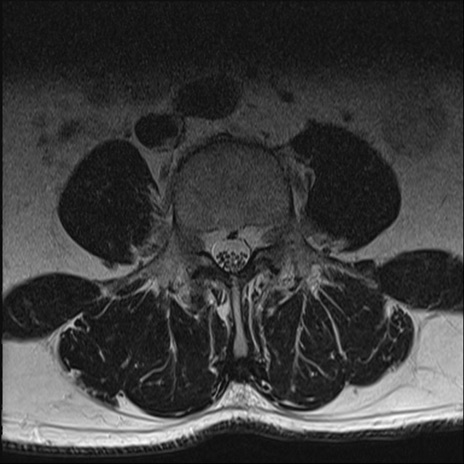

【整形】TIPS症例2 腰椎MRI T2WI(横断像)

【症例】70歳代男性

【主訴】左下肢痛

【現病歴】2週間前くらいから腰痛、左下肢痛あり。左臀部から大腿、下腿外側のしびれが常時ある。歩行とともに同部位の痛みあり。

【身体所見】Lasegue70-/60+、Bragard-/±、PTR ±/±、ATR -/-、IP 5/5、TA 5/4、TS 5/5、EHL 右第1足趾なし/3、FHL 5/5、hypersthesia(-)、足背動脈触知良好

異常所見と診断は?